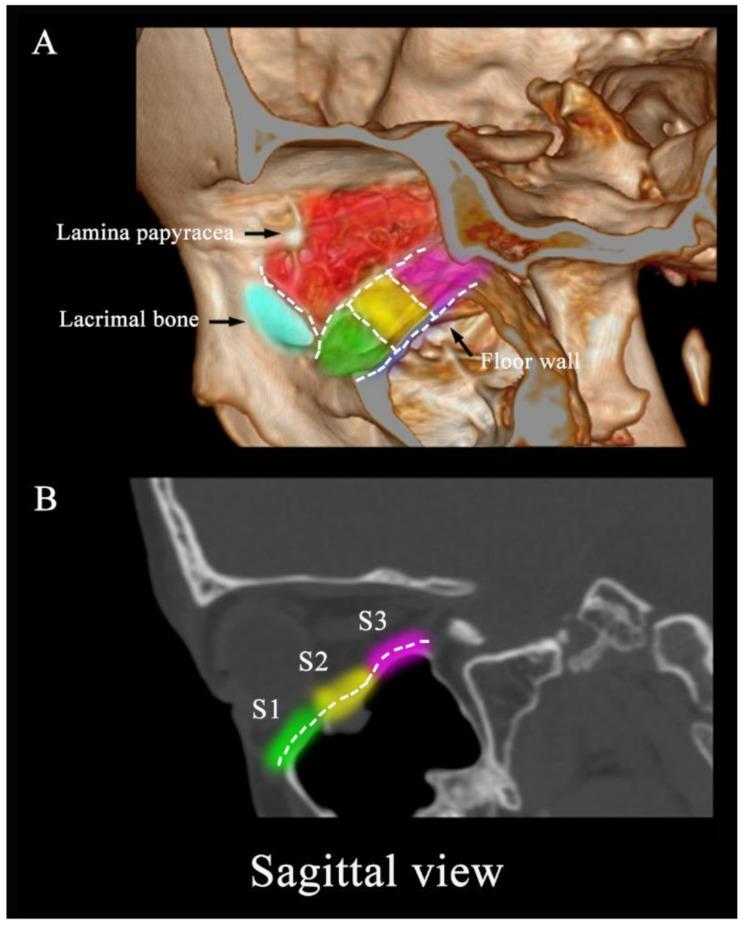

Methods: We retrospectively analyzed clinical and imaging data from 155 patients who experienced orbital fractures at our center between 2021 and 2023. Orbital fracture sites were classified as C/S/A according to imaging: the lacrimal bone was named as A1, the bony structure behind lamina papyracea as A2 and the lateral wall of the orbit (including the zygomatic bone and the greater wing of sphenoid) was appointed as A3 in the axial view; the orbital floor was divided into three equal parts as S1-S3 in the sagittal view; the frontal process of maxilla was designated as C1, the intermediate central midface between frontal process of maxilla and zygomaticomaxillary suture as C2 and the structure between the zygomaticofrontal suture and the zygomaticomaxillary suture was named as C3. First, we examined clinical characteristics, including age, gender, fracture position, as well as follow-up data on fracture location and diplopia duration. Next, we assessed the correlation between orbital fracture location (C/S/A) and diplopia occurrence. Lastly, we used a multivariable logistic regression model to evaluate predictors associated with the occurrence and location of diplopia in orbital fractures.